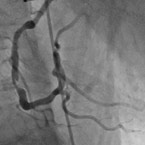

Entfalteter Ballon während der PTCA